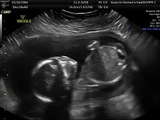

baby Ed

10 years ago